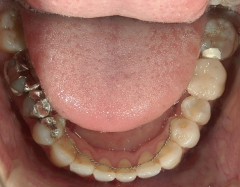

矯正歯科 治療前矯正歯科 治療前

矯正歯科 治療前 外科手術併用(コルチコトミー)、非抜歯

矯正_灰色.pngno.7_6967_治療前_下_01.jpg矯正_灰色.png